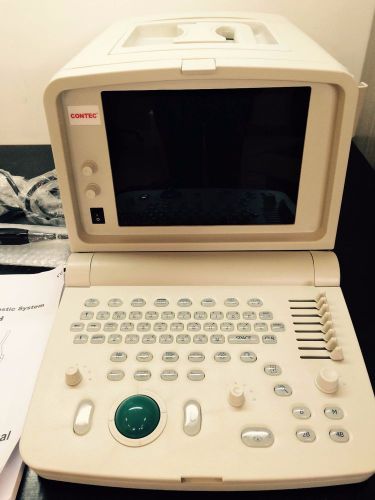

CMS600H Veterinary Portable B-Ultrasound Scanner+ 7.5Mhz RECTAL